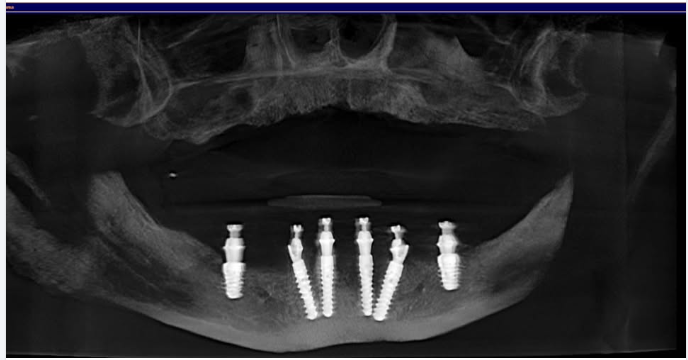

Hình ảnh 1 ca bị mất R34,37 được Bác sĩ tư vấn cắm Implant Mis C1 tại chi nhánh Huỳnh Văn Bánh, Phú Nhuận.

P/s: Image of a case with missing teeth R34,37 advised by the dentist for Mis C1 Implants at Huỳnh Văn Bánh branch, Phú Nhuận.